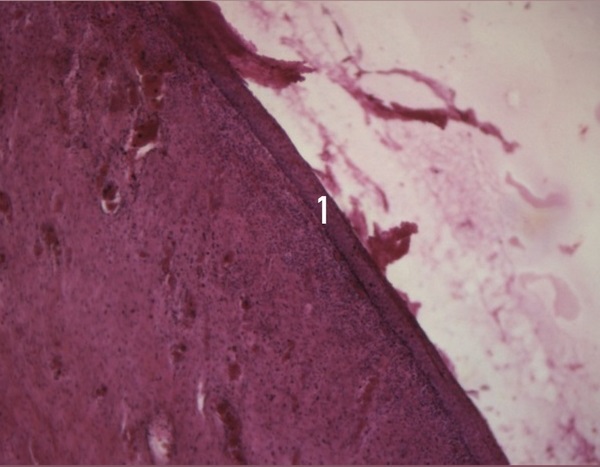

Рисунок 1 - Деструктивно-атрофические изменения слизистой оболочки шейки матки указаны на рисунке цифрой 1

Примечание: окрашивание гематоксилином и эозином; увеличение х25